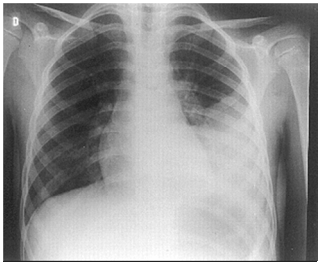

A sua radiografia de tórax mostra: